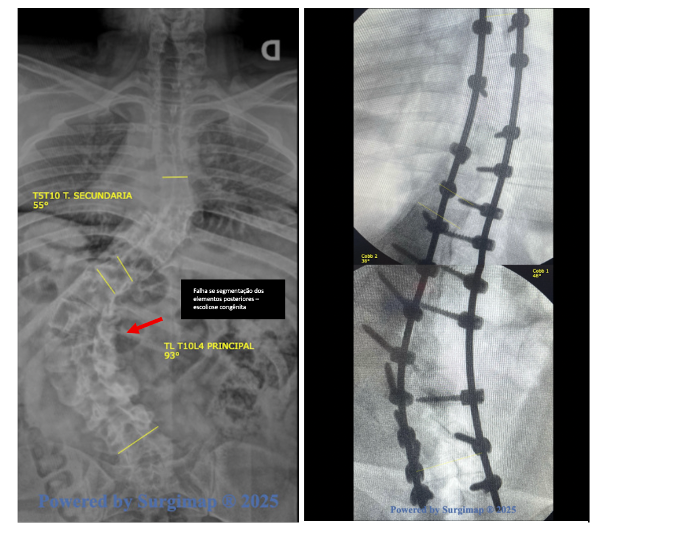

Escoliose congênita (falhas de formação ou segmentação vertebral)

Já a escoliose congênita é um tipo mais raro de escoliose, presente desde o nascimento. Estima-se que ocorra em aproximadamente 1 a cada 1.000 a 2.000 nascidos vivos. Ela se desenvolve porque, ainda durante a gestação, algumas vértebras não se formam adequadamente ou não se separam corretamente umas das outras.

Esse processo acontece muito cedo no desenvolvimento do bebê, quando a coluna ainda está sendo “construída”. Por esse motivo, a escoliose congênita não está relacionada à postura, uso de mochila, prática esportiva ou hábitos do dia a dia.

Como o problema está na estrutura óssea da vértebra, a curva apresenta algumas características típicas:

- não se corrige quando o médico tenta endireitar manualmente a coluna;

- não melhora com exercícios ou mudanças de posição;

- tende a ser mais rígida e menos flexível do que outros tipos de escoliose.

Para estes casos, a chance de progressão da curva ao longo do crescimento depende diretamente do tipo de anomalia vertebral presente. De forma geral, podem ocorrer dois grandes grupos de alterações:

- falhas de segmentação, quando as vértebras não se separam adequadamente;

- falhas de formação, quando a vértebra se forma de maneira incompleta ou assimétrica, como nas hemivértebras.

Cada um desses padrões apresenta um comportamento evolutivo diferente, o que torna essencial a avaliação individualizada.